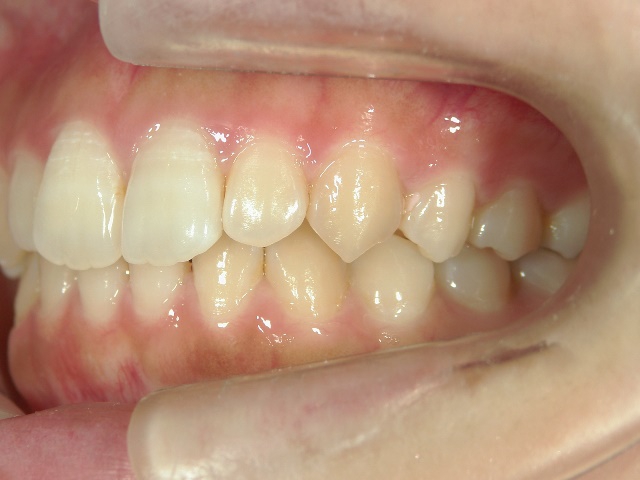

矯正歯科 治療前 右

矯正歯科 治療後 右